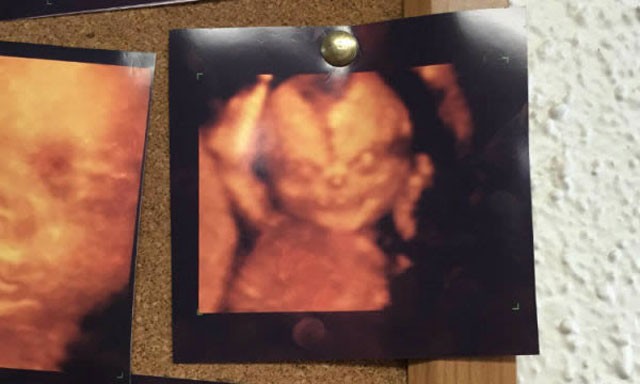

Karnında kalp şekli olan bebek

Bebeklerini görme heyecanıyla doktora gidip ultrasonda bu görüntüleri gören ebeveynlerin korkmuş olabileceğini tahmin ediyoruz.